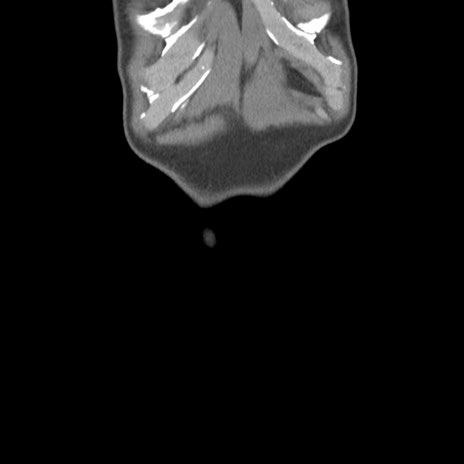

脂肪ウインドウ